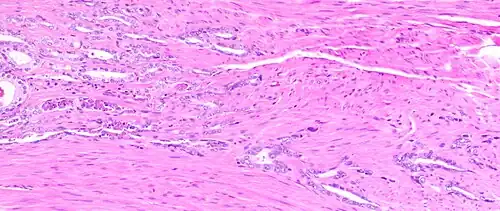

The prostate consists of glandular and connective tissue.[2] Tall column-shaped cells form the lining (the epithelium) of the glands.[2] These form one layer or may be pseudostratified.[4] The epithelium is highly variable and areas of low cuboidal or flat cells can also be present, with transitional epithelium in the outer regions of the longer ducts.[10] Basal cells surround the luminal epithelial cells in benign glands. The glands are formed as many follicles, which drain into canals and subsequently 12–20 main ducts, These in turn drain into the urethra as it passes through the prostate.[4] There are also a small amount of flat cells, which sit next to the basement membranes of glands, and act as stem cells.[2]

The connective tissue of the prostate is made up of fibrous tissue and smooth muscle.[2] The fibrous tissue separates the gland into lobules.[2] It also sits between the glands and is composed of randomly orientated smooth-muscle bundles that are continuous with the bladder.[11]

Microscopic glands of the prostate -

Microanatomy of a prostatic gland, showing both luminal cells and surrounding basal cells. H&E stain. -

Histology of normal prostate, H&E stain, with benign features: Glands are rounded to irregularly branching, with an inner layer of epithelial cells surrounded by an outer layer of basal cells. They are surrounded by ample stroma. -

Histology of prostate with gradually increasing simple atrophy from left to right, H&E stain. Crowding and angulation may mimic that of adenocarcinoma, but there is nuclear basophilia rather than atypia, and occasional basal cells can still be seen.